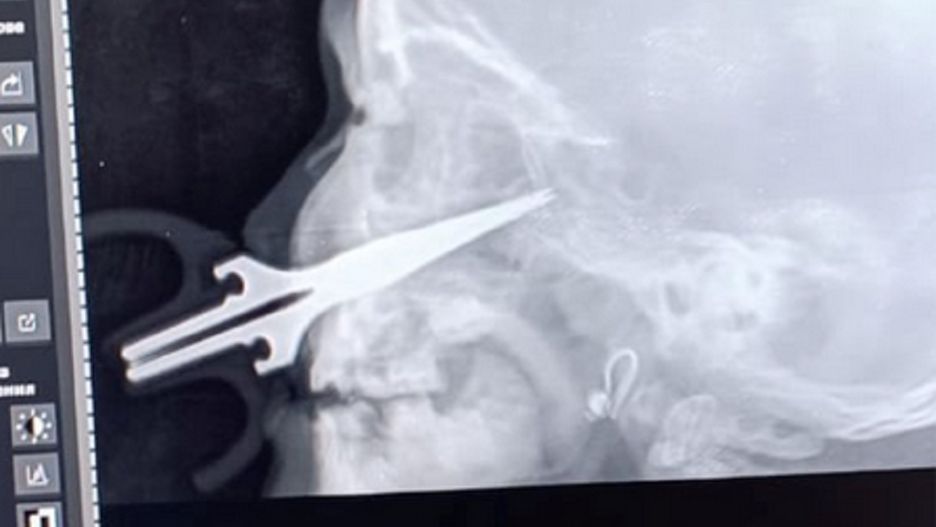

Ta zabawa dla 5-latki mogła okazać się tragiczna w skutkach. Lekarze z Kirgistanu ze szpitala w Oszu przeprowadzili skomplikowaną operację usunięcia nożyczek z twarzy dziewczynki. 5-latka zraniła się podczas zabawy. Przedmiot wbił się w policzek na około 7 centymetrów.

5-letnia dziewczynka bawiła się w domu, trzymając w rękach nożyczki. Przez kilka chwil pozostała bez opieki i w tym czasie spadła ze stołu i upadła tak mocno, że wbiła się w ostrą część przedmiotu.

Nożyczki przebiły skórę na prawym policzku i przez zatokę szczękową wbiły się w czaszkę na około 7 centymetrów.

Jak poinformowało kirgiskie Ministerstwo Zdrowia, rodzice przywieźli dziewczynkę do Międzyregionalnego Szpitala Dziecięcego w Osz 9 marca. Dziewczyna została przyjęta na oddział otolaryngologii, który zajmuje się urazami głowy oraz szyi.

Po szybciej konsultacji, lekarze zdecydowali się na operację, którą poprowadził ordynator oddziału Umutbek Pazyłow. Medycy przeprowadzili skomplikowaną operację i usunęli nożyczki z czaszki.

Na szczęście dla dziecka, okoliczne duże tętnice nie zostały naruszone, w przeciwnym razie życie dziecka byłoby poważnie zagrożone. Obecnie stan dziecka jest dobry, dziewczynka jest przygotowywana do wypisu ze szpitala - poinformowało kirgiskie Ministerstwo Zdrowia.